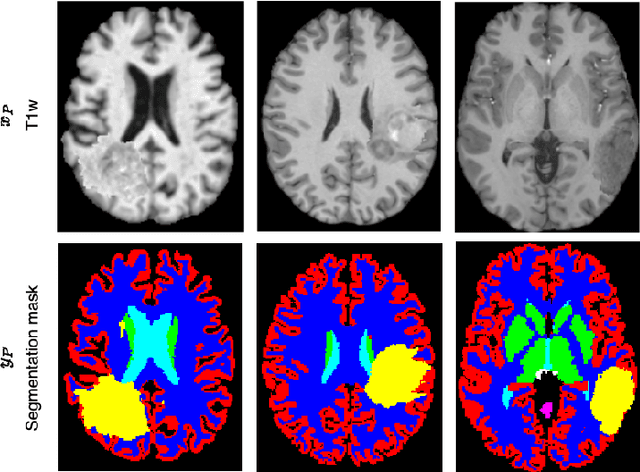

Abstract:Segmenting healthy tissue structures alongside lesions in brain Magnetic Resonance Images (MRI) remains a challenge for today's algorithms due to lesion-caused disruption of the anatomy and lack of jointly labeled training datasets, where both healthy tissues and lesions are labeled on the same images. In this paper, we propose a method that is robust to lesion-caused disruptions and can be trained from disparately labeled training sets, i.e., without requiring jointly labeled samples, to automatically segment both. In contrast to prior work, we decouple healthy tissue and lesion segmentation in two paths to leverage multi-sequence acquisitions and merge information with an attention mechanism. During inference, an image-specific adaptation reduces adverse influences of lesion regions on healthy tissue predictions. During training, the adaptation is taken into account through meta-learning and co-training is used to learn from disparately labeled training images. Our model shows an improved performance on several anatomical structures and lesions on a publicly available brain glioblastoma dataset compared to the state-of-the-art segmentation methods.